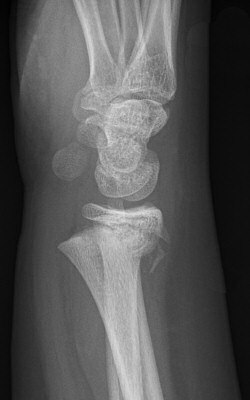

Dorsalbockad distal radiusfyseolys Salter-Harris typ 2 före och efter reposition

Dorsalbockad distal radius- och/eller ulnafyseolys (SH2)

Behandla icke-kirurgiskt om: [1]

- < 10 år för flickor, < 12 år för pojkar:

- ≤ 30° vinkelfelställning jämfört med anatomiskt läge

och

- ≤ 1/2 benbredds ad latus

- ≥ 10 år för flickor, ≥ 12 år för pojkar:

- ≤ 20° vinkelfelställning jämfört med anatomiskt läge

- ≤ 1/4 benbredds ad latus dorsalt

Icke-kirurgisk behandling:

- Semicirkulärt gips på underarmen (hög gipsskena hos små barn, det ramlar annars av), alltså bredare gips som ger trepunktstöd. Dorsalt vid dorsalbockning, volart med handleden dorsalextenderad vid volarbockning.

- Återbesök med röntgenkontroll efter 5-7 dagar [1], förutom vid odislocerad fraktur, då behövs inget återbesök.

- Vid försämrat läge men inom gränsvärde vid återbesöket: ny röntgenundersökning efter ytterligare 5 dagar. [1]

- Avgipsning i hemmet 3-4 veckor efter skadan. [1]

- Undvik risker 2 veckor efter avgipsning. [1]